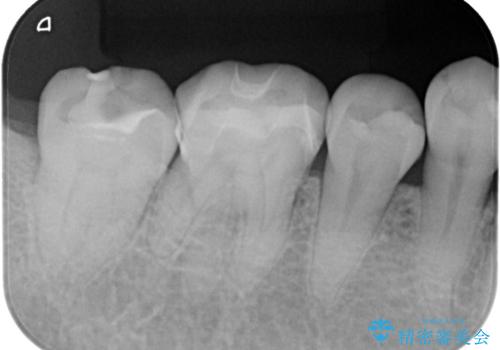

歯間に食渣がつまるのをどうにかしたいとの主訴のもと、治療を開始しました。フロスを通してみると、コンタクトは無く0.25mm程のスペースがありました。

メタルインレーを歯冠色のものに変えたいという希望もあったため、セラミックインレーでのやり替えによるコンタクトの再現をしています。

また、近心側にう蝕が認められたため窩洞の範囲を元々入っていたメタルインレー窩洞よりも広げています。

セラミックインレーセット時ラバーダム防湿を行っています。